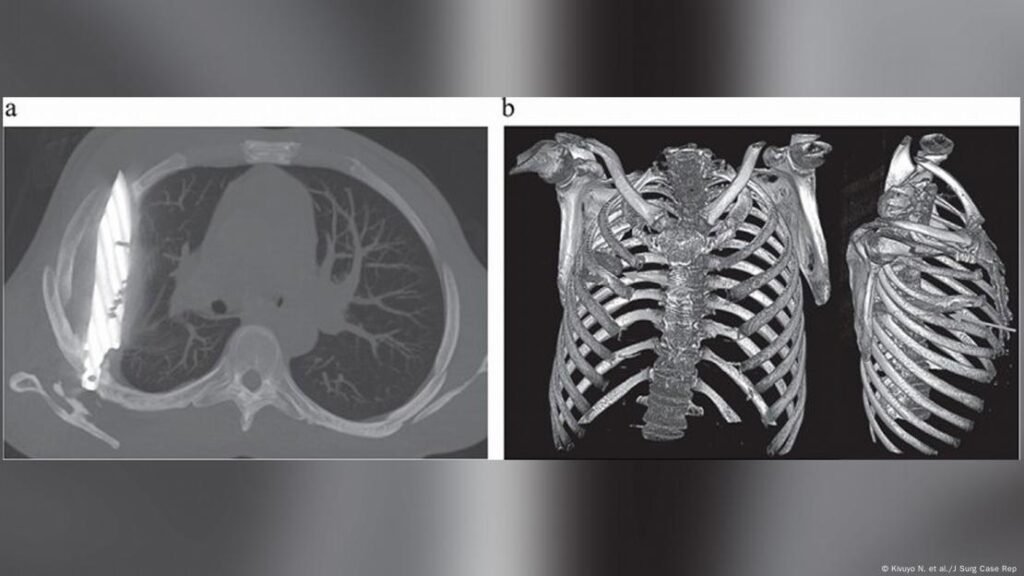

Cuando los médicos examinaron al paciente, observaron que la parte frontal del tórax derecho estaba hundida y que ese lado no se expandía del todo al respirar. Una radiografía reveló la impactante verdad: había «un objeto metálico retenido» dentro de su tórax. La tomografía computarizada confirmó los detalles: una hoja completa de cuchillo atravesaba su cavidad torácica.

Había entrado por la espalda, cerca de la escápula derecha, deslizándose entre la quinta y sexta costilla, y su punta se encontraba entre la tercera y cuarta costilla del frente. El arma estaba rodeada de pus y tejido necrótico, y las imágenes mostraron fracturas ya curadas en la escápula y varias costillas.